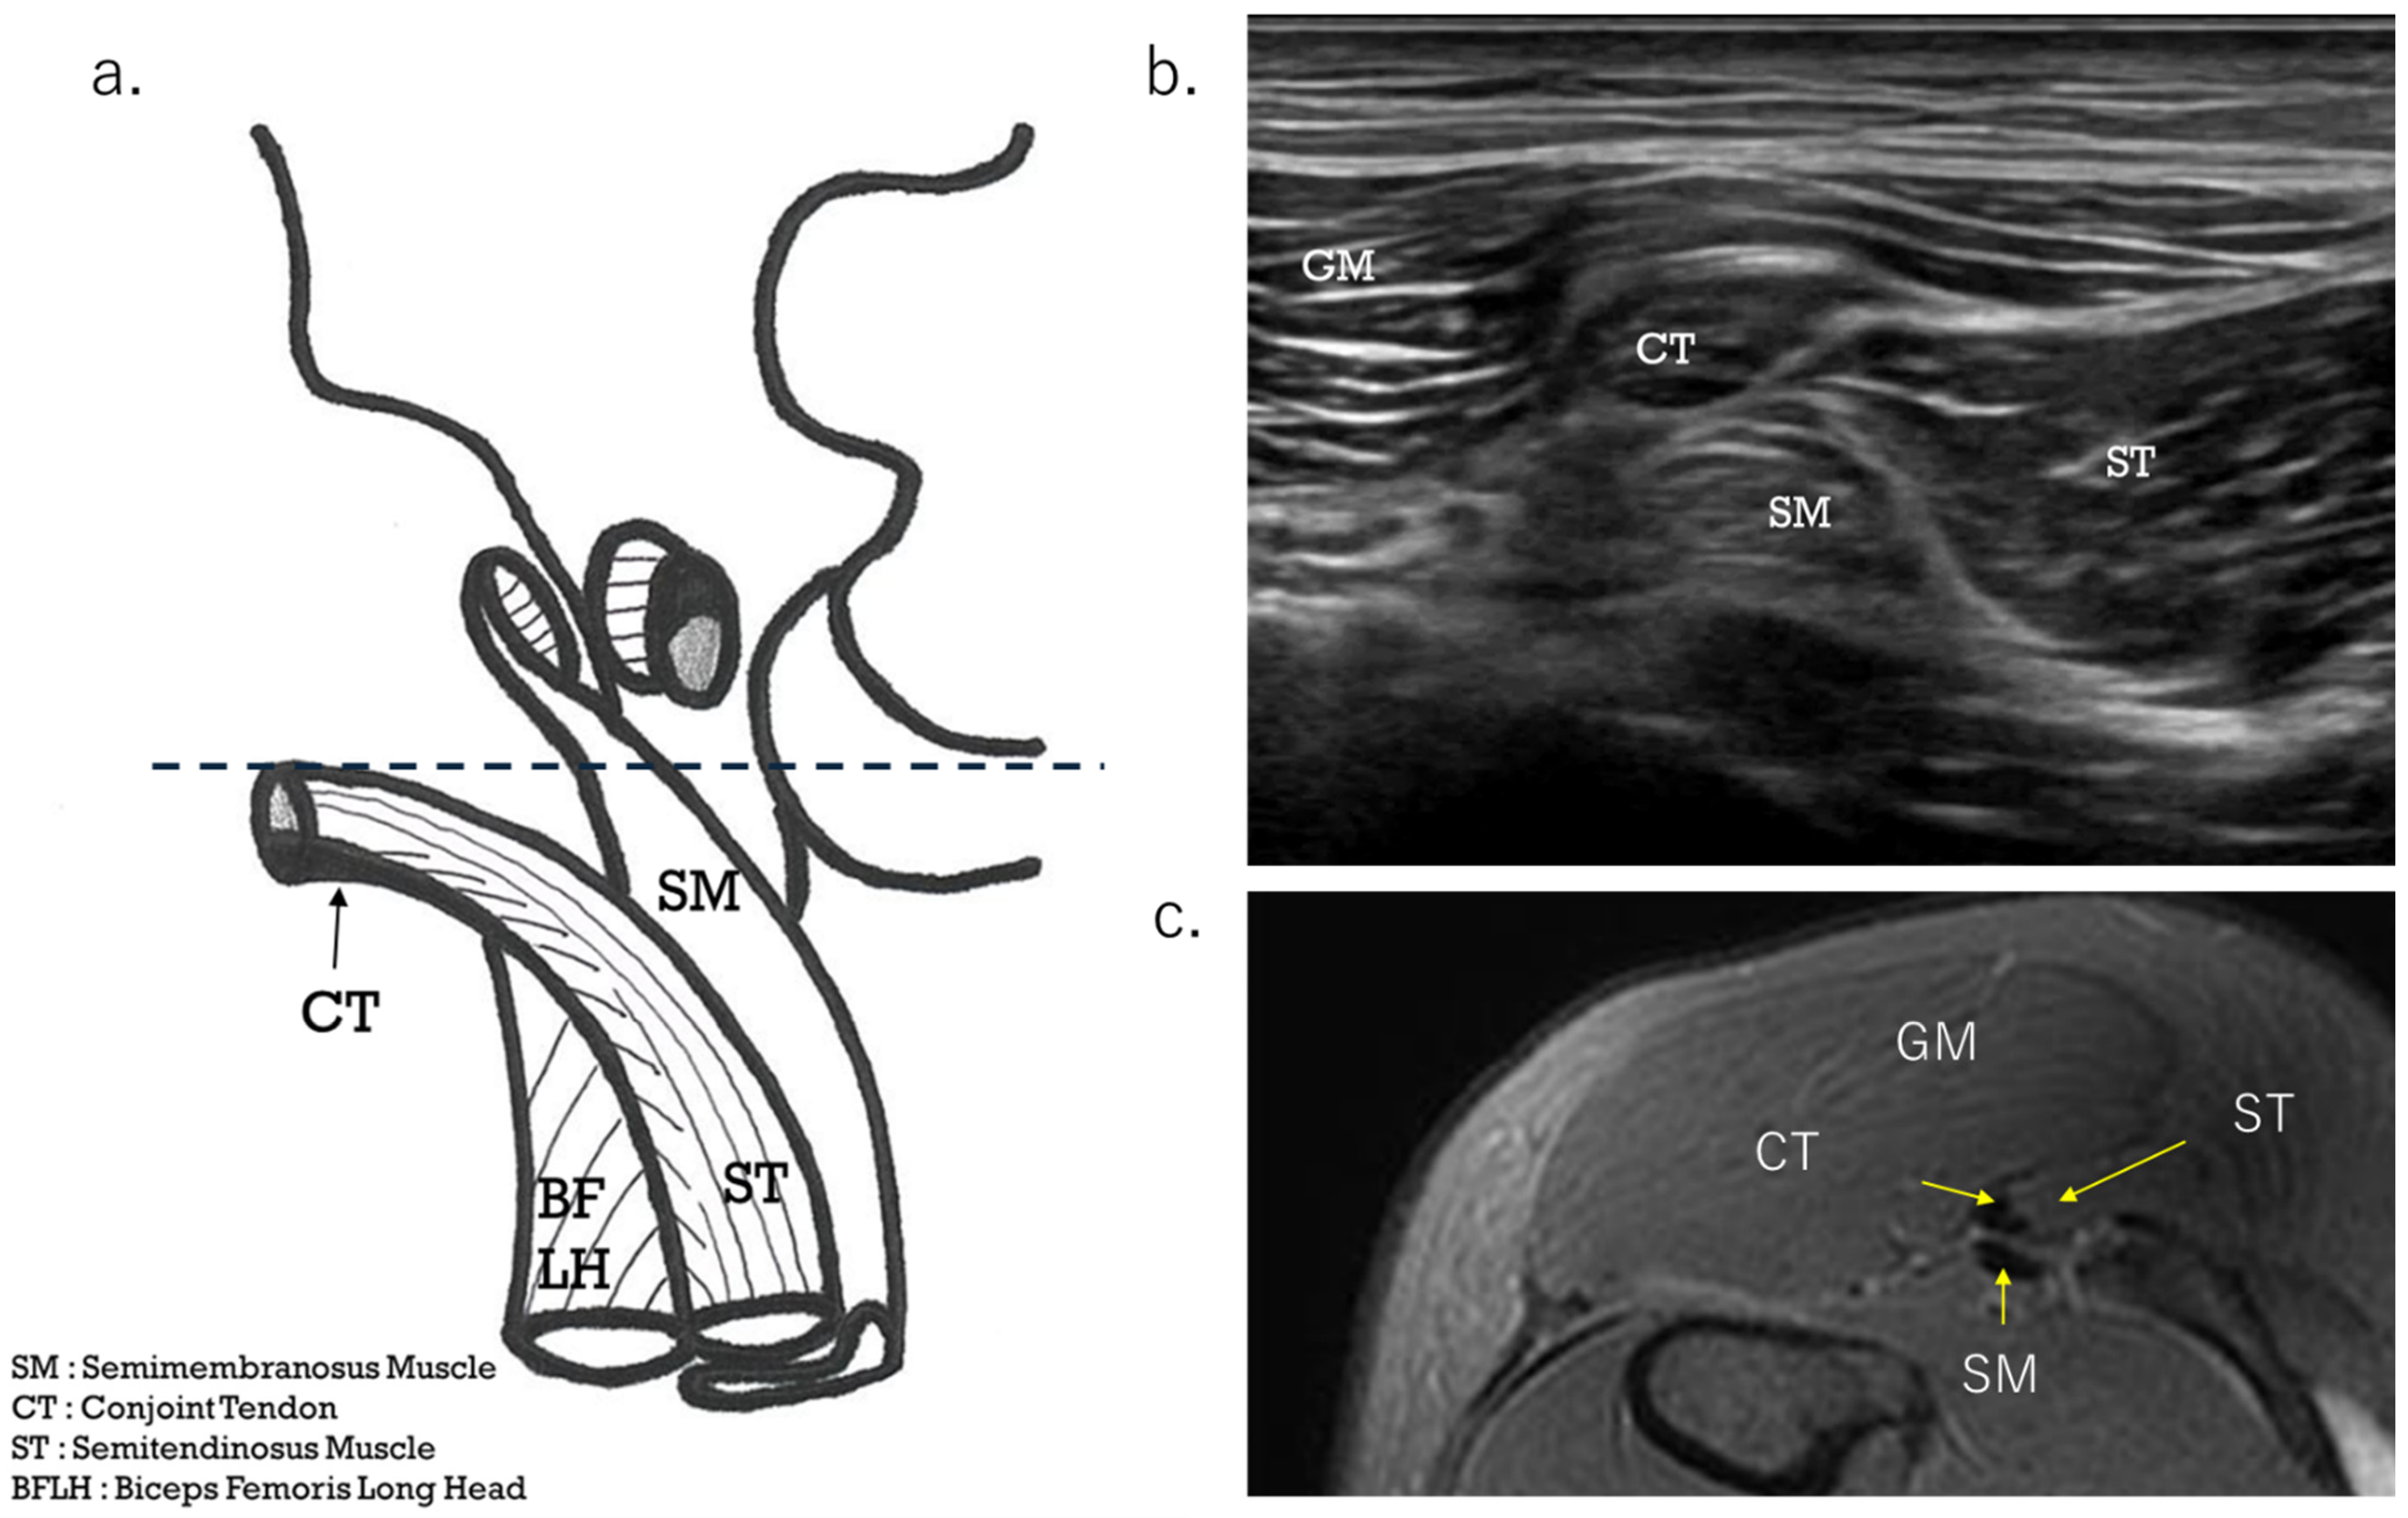

The diagnostic procedure began with an ultrasound scan. If there was tenderness around the ischial tuberosity, the area in the short axis from a slightly more distal position was observed at the level where CT and SMT intersect (Figure 2a, dashed line). The severity of the injury to the CT tear was assessed by following the short-axis view from distal to proximal up to the ischial tuberosity. The avulsion or tear site was confirmed in the long-axis view. The distance from the tear to the ischial tuberosity was then clear. If there was tenderness around the proximal musculotendinous junction, it was observed whether any hematoma was present on both sides or only on one side on CT, and the uneven thickness of CT in the short axis was checked. The probe was then placed in the direction of the muscle fibers at the musculotendinous junction to determine the injury type and severity of damage to the tendons and muscle fibers (in the long-axis view). In cases where it was difficult to judge, the decision was made by comparing it with the healthy side.

The HMC is a biarticular muscle complex made up of four muscles, three of which originate from the ischial tuberosity with the CT and SMT. The ST is composed of muscle fibers that originate both directly from the ischium and from the conjoint tendon (CT), whereas all BFLH muscle fibers originate from the CT [2,3,8,10] (Figure 2a). Type I injuries are defined as a tear of the CT. As in the diagnostic procedure described above, by carefully observing via ultrasound, it is possible to determine the location of the damage. When performing an ultrasound evaluation of damage to the ischial tuberosity and surrounding area of the origin tendon, such as in CT and SMT, it is easier to see the detached and coiled appearance of the damaged tendon and find swelling if the evaluation is performed at the level where the CT and SMT intersect (Figure 2a, dashed line). The characteristics of the ultrasonic short-axis findings in cases of CT injury and SMT injury and injury to both the CT and SMT are shown in Figure 3. The position of the attachment points of the SMT, CT, and ST muscle fibers are important. The SMT runs through the deep layer of the CT and attaches to the lateral side of the ischial tuberosity. The CT attaches to the medial side of the SMT, and the muscle fibers of the ST attach further to the medial side. The area where the SMT attaches is difficult to visualize using ultrasound in athletes with well-developed gluteal muscles or those with a lot of subcutaneous fat. In such cases, it is useful to evaluate by scanning from the points in Figure 2 and Figure 3 towards the proximal end. The short-axis image of the ischial tuberosity is shown next, in contrast to the MRI image (Figure 4 and Figure 5). In this study, detection by ultrasound was possible for both the BF-ST complex and SM in all but one case, which was a minor injury without conjoint tendon tortuosity or hematoma.

Figure 2. Short-axis view at the level of the CT and SM tendon cross. (a) Schema showing CT-ST and SMT flipped from the attachment point. The position shows the relationship between the CT and the SM tendon (SMT). When the ultrasound probe is scanned from the distal to the proximal end, the SMT travels from the medial side to the lateral side, through a deeper layer than the CT. As for the ischial tuberosity attachment point, the SMT is located at the lateral side, with the CT and ST muscle fibers located at the medial side. (b) Ultrasound short-axis image at the point where the CT and SMT intersect. The CT and SMT ellipses are lined up vertically. (c) This is an axial MRI image (T2-weighted image with fat suppression) of the same level.